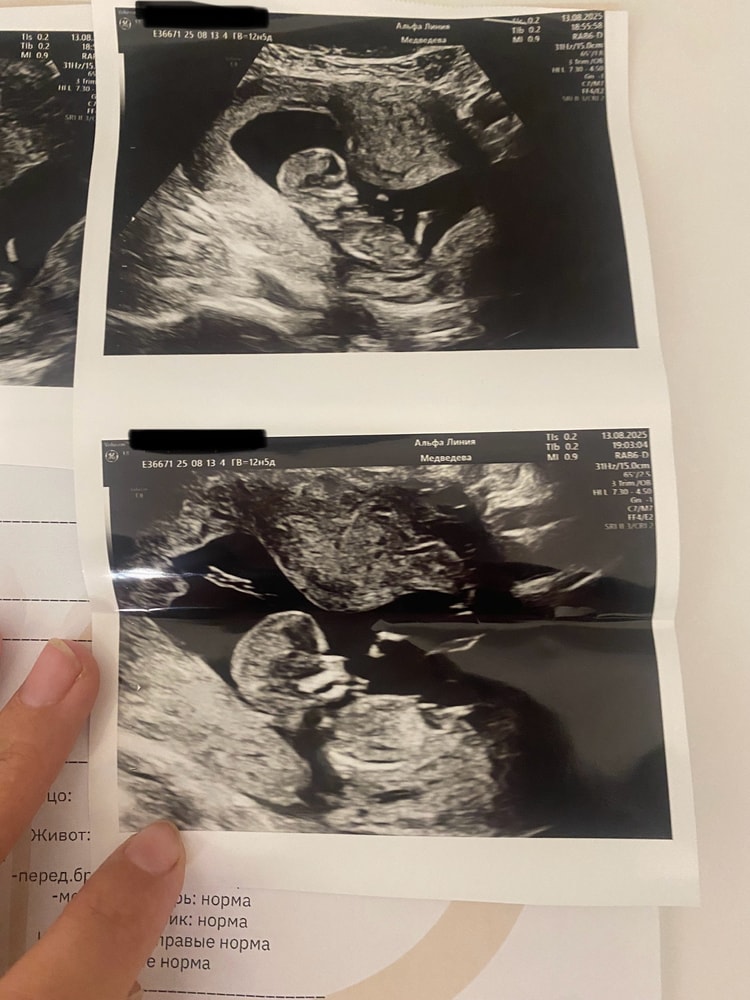

УЗИ, КТГ, доплерОпытные мамочки, на сроке 13 неделе делала УЗИ, как думаете, каков пол?

Опытные мамочки, на сроке 13 неделе делала УЗИ, как думаете, каков пол?